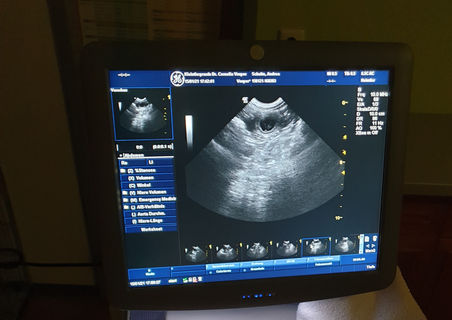

Hurra!!! Caci ist trächtig!

Letzte Woche waren wir beim Tierarzt zum Ultraschall und konnten einige Welpenanlagen sehen.

Hier einige Bilder:

Bei weiterem guten Verlauf, erwarten wir Cacis Welpen um den 23.02.2021.